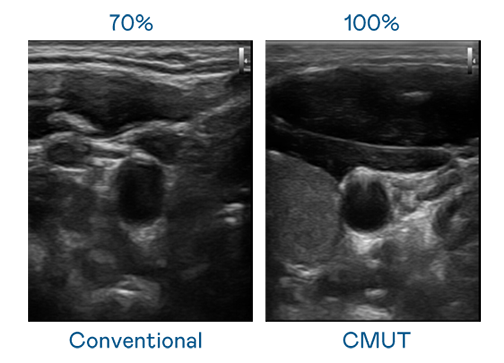

CMUT 技术是一种用电容式微机电元件来产生超音波讯号的技术。与传统 PZT 压电式技术相比,CMUT 频宽增加 30%,更宽频的超音波讯号让影像解析度大幅提升,是实现高影像品质医疗超音波扫描、促进精准医疗发展的关键技术。

超音波影像的解析度高低,首先取决于探头能发出的讯号频宽。d88尊龙z6 CMUT 可提供高清晰的超音波讯号,提供高频宽、高灵敏度、影像纹理细节更高的超音波影像,协助医护人员缩短影像判读时间及利用精准的医疗影像进行诊断。